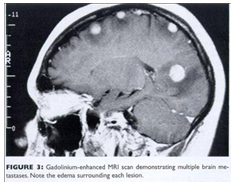

L'IRM : ou l'Imagerie par Résonance Magnétique, développé en 1980, se base sur la mesure la résonnance des protons soumis à un champ magnétique pour différentes parties du corps (cerveau, moelle épinière, moelle osseuse, colonne vertébrale…)

Le patient, allongé et enfermé dans une sorte de gros tube, est en contact avec le manipulateur qu'il peut appeler. L'appareil prend un grand nombre de clichés qui sont analysés par l'ordinateur. Cet examen d'une durée d'une demi-heure environ, est indolore, il n’entraine donc aucune irradiation. L’image est plus fine et plus précise que le scanner.